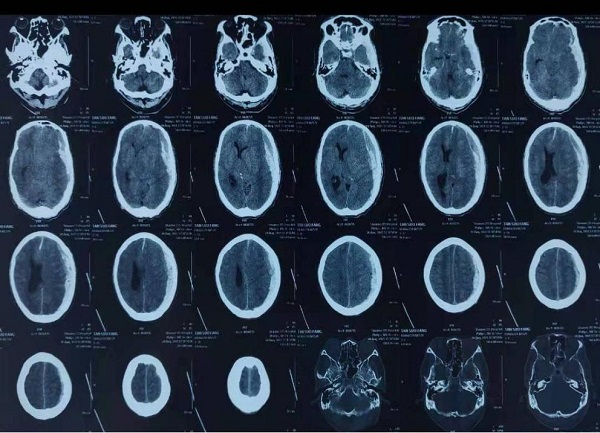

57岁谭先生3天前不慎摔伤,当时自觉无特殊不适感,并未在意,直至出现头痛、呕吐症状才就诊当地县医院,头颅CT检查提示急性硬膜下血肿,此时意识已处于深昏迷状态,双侧瞳孔大小不等。接到医院急诊的电话,神经重症卒中监护室谢国强副主任立即带领科室医生到急诊科,等待患者到来,患者入急诊科后,立即开通绿色通道,争分夺秒,为急诊手术做准备。此时头颅CT提示急性硬膜下血肿,量约100ml,诊断为脑疝。